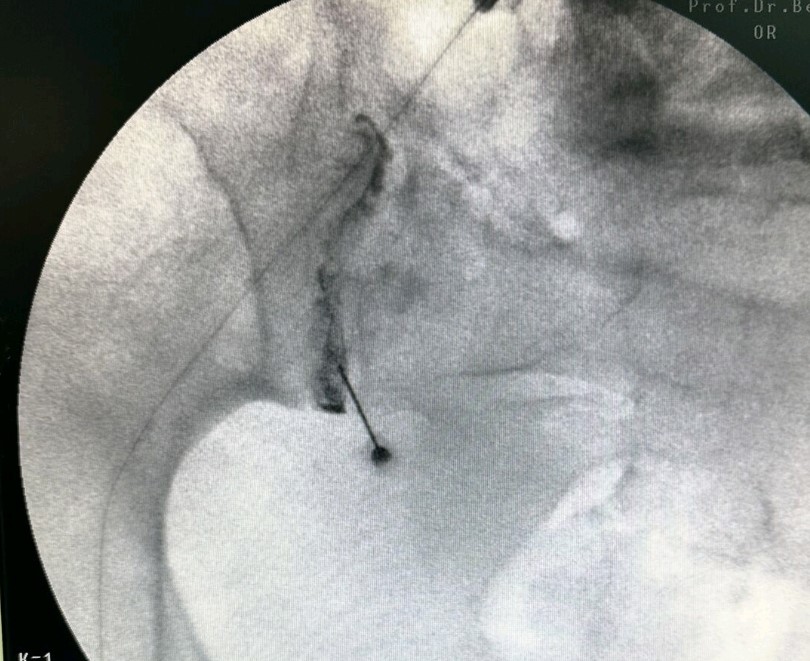

Στην ουραία επισκληρίδιο έγχυση υπό ακτινοσκοπική καθοδήγηση, εισάγεται ένας καθετήρας μέσω του ιερού τρήματος και προωθείται έως το επίπεδο στης κατώτερης οσφυϊκής μοίρας, όπου γίνεται η έγχυση διαλύματος τοπικού αναισθητικού και στεροειδούς.